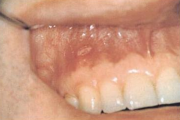

Suu limaskesta haavandid

- Alati tuleb kontrollida hambaproteese. – Haavandi põhjuseks võib olla odontoloogiline infektsioon. – Igal juhul tuleb arvestada vähi võimalusega. Reeglina tuleb võtta biopsia haavanditest, mis kahe nädala jooksul ei parane. – Konsulteerida hambaarstiga; patsiendid, kellele tuleb teha Loe edasi »